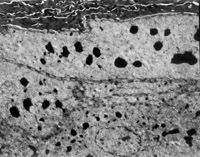

傷后12h急診入院,檢查雙下肢為淺Ⅲ度燒傷。創(chuàng)面表皮已壞死剝脫,真皮層變性壞死呈蠟黃色和蠟白色相間(圖5-3-1)。取局部組織做病理切片檢查,顯示上皮組織全層壞死,真皮層膠原纖維變性,結(jié)構(gòu)紊亂,微循環(huán)瘀滯(圖5-3-2)。

2. 電鏡觀察 受傷當(dāng)日上皮組織變性壞死,可見(jiàn)單核細(xì)胞核偏移、固縮,并有吞噬現(xiàn)象(圖5-3-12)。

5-3-12 燒傷當(dāng)日,單核細(xì)胞核偏移,固縮,并有吞噬現(xiàn)象  TE×8000